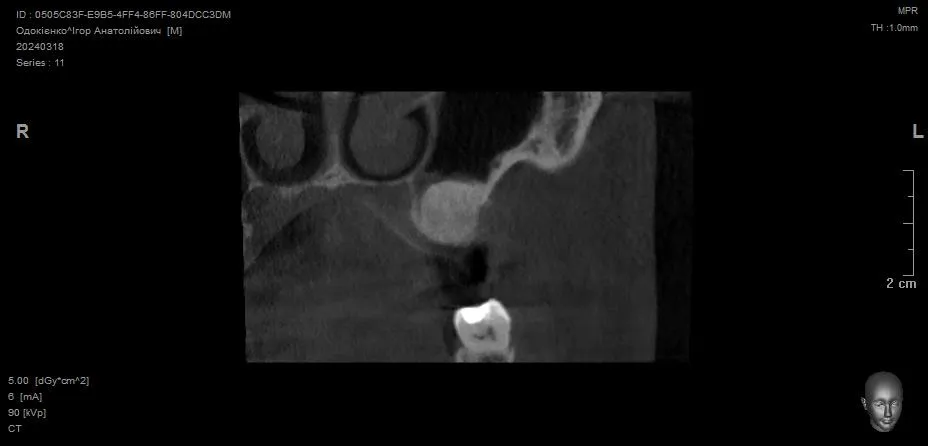

Відкритий синус-ліфтинг